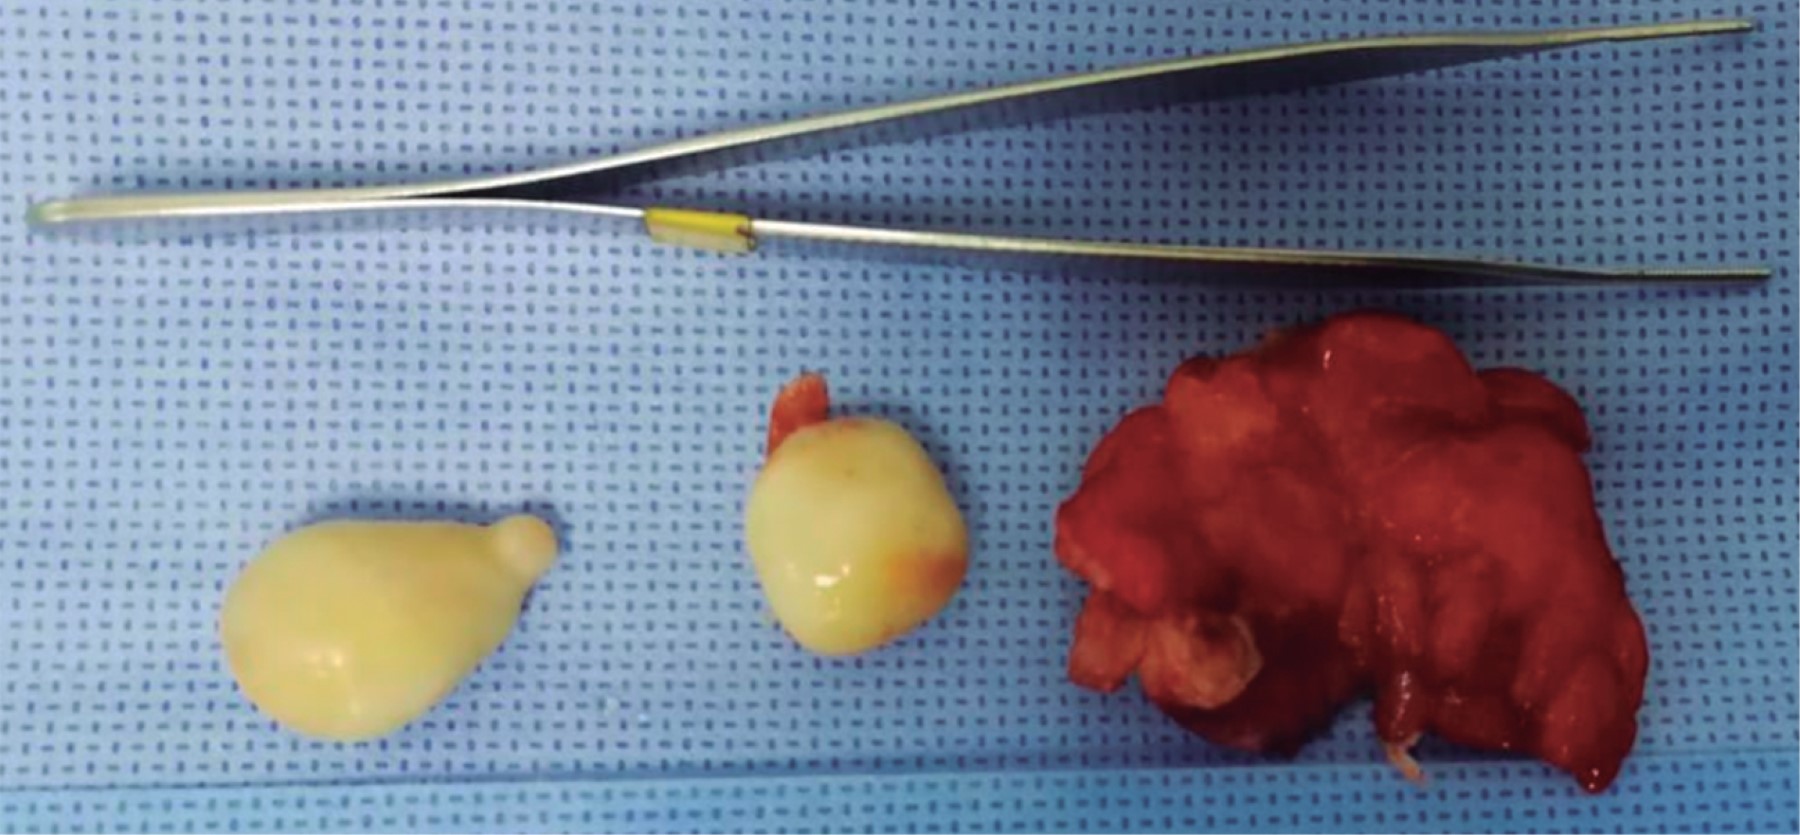

Hombre en la novena década de la vida, con dolor abdominal de 72 horas de evolución, con predominio a nivel de la fosa iliaca derecha (FID), asociado a episodio de bacteriemia, hiporexia, náusea, vómito y evacuaciones líquidas. Abdomen con dolor a la palpación en la FID, apendiculares positivos, peristalsis presente e hiperactiva, con datos de irritación peritoneal. Leucocitosis de 11.2 × 103 ul, con desviación a la izquierda: neutrofilia de 86.9%. La tomografía abdomino-pélvica con medio de contraste intravenoso (Figura 1) mostró el apéndice cecal con datos de proceso inflamatorio agudo. Se realizó apendicectomía abierta por incisión tipo McBurney. Al ingresar a la cavidad abdominal se encontraron de manera incidental tres cuerpos peritoneales libres, los cuales se enviaron a estudio histopatológico, junto con el apéndice cecal resecado (Figura 2).

El análisis patológico macroscópico reportó tres neoformaciones ovoides de 17 × 15 × 10 mm, 16 × 10 × 10 mm y 14 × 10 × 10 mm cada uno, de superficie lisa, amarilla y firme (Figura 3); al corte son sólidos, con una zona periférica gris blanquecina de 4 mm de espesor y una zona central amarillenta de consistencia firme (Figura 4).